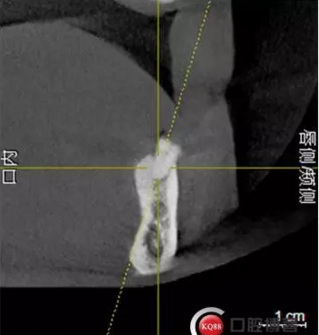

檢查:上頜無(wú)牙頜假牙穩(wěn)定性尚可,下頜3435364243殘根;33殘冠1-2度松動(dòng),其他牙齒缺失;CBCT檢查:下頜牙槽骨前牙區(qū)骨高度足,后牙區(qū)骨高度最低為8mm,骨寬度足。

1)術(shù)前檢查,拍攝臨床照片及CBCT檢查,制取活動(dòng)義齒參考模型,指導(dǎo)后期最終修復(fù)的牙齒排列

2)術(shù)前準(zhǔn)備及手術(shù)過(guò)程,測(cè)量血壓及血糖,簽種植知情同意書;嚴(yán)格遵循無(wú)菌操作,局麻下采用微創(chuàng)技術(shù)于323436分別植入osstem4.0X10,4.0X10,4.5X7; 434446分別植入osstem4.0X1O,4.0X10,4.5X7.初期穩(wěn)定性均達(dá)到了35N.CM以上;嚴(yán)密縫合,止血,種植體位點(diǎn)和方向與設(shè)計(jì)一致。